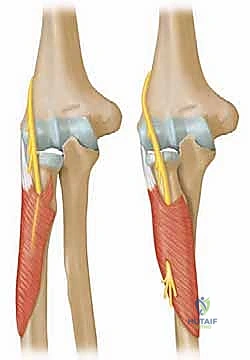

لفهم مدى خطورة هذه الكسور وكيفية علاجها، يجب أولاً فهم التشريح الدقيق للمنطقة. يقع رأس الكعبرة في الجزء العلوي (القريب) من عظم الكعبرة، وهو ذو شكل أسطواني يشبه القرص، ومغطى بغضروف زجاجي أملس.

وظائف رأس الكعبرة في المرفق:

1. التمفصل مع عظم العضد (Humeroradial Joint): يتمفصل السطح العلوي المقعر لرأس الكعبرة مع "الرؤيس" (Capitellum) الخاص بعظم العضد. هذا المفصل ضروري لحركات الثني والمد.

2. التمفصل مع عظم الزند (Proximal Radioulnar Joint): يتمفصل المحيط الجانبي لرأس الكعبرة مع "الثلمة الكعبرية" في عظم الزند. هذا المفصل هو المسؤول الأول عن حركات دوران الساعد (قلب راحة اليد لأعلى ولأسفل).

3. الاستقرار الميكانيكي (Secondary Stabilizer): يعمل رأس الكعبرة كداعم أساسي (مثبت ثانوي) ضد قوى الانحناء الجانبي (Valgus stress) التي تتعرض لها الذراع، خاصة إذا كان الرباط الجانبي الزندي (MCL) مصاباً.

عنق الكعبرة هو الجزء الأضيق الذي يربط رأس الكعبرة بجسم العظم، وهو الموقع الذي تتصل فيه المحفظة المفصلية. أي كسر في هذه المنطقة الدقيقة يعطل هذه الميكانيكا الحيوية ويؤدي إلى ألم شديد وفقدان للحركة.